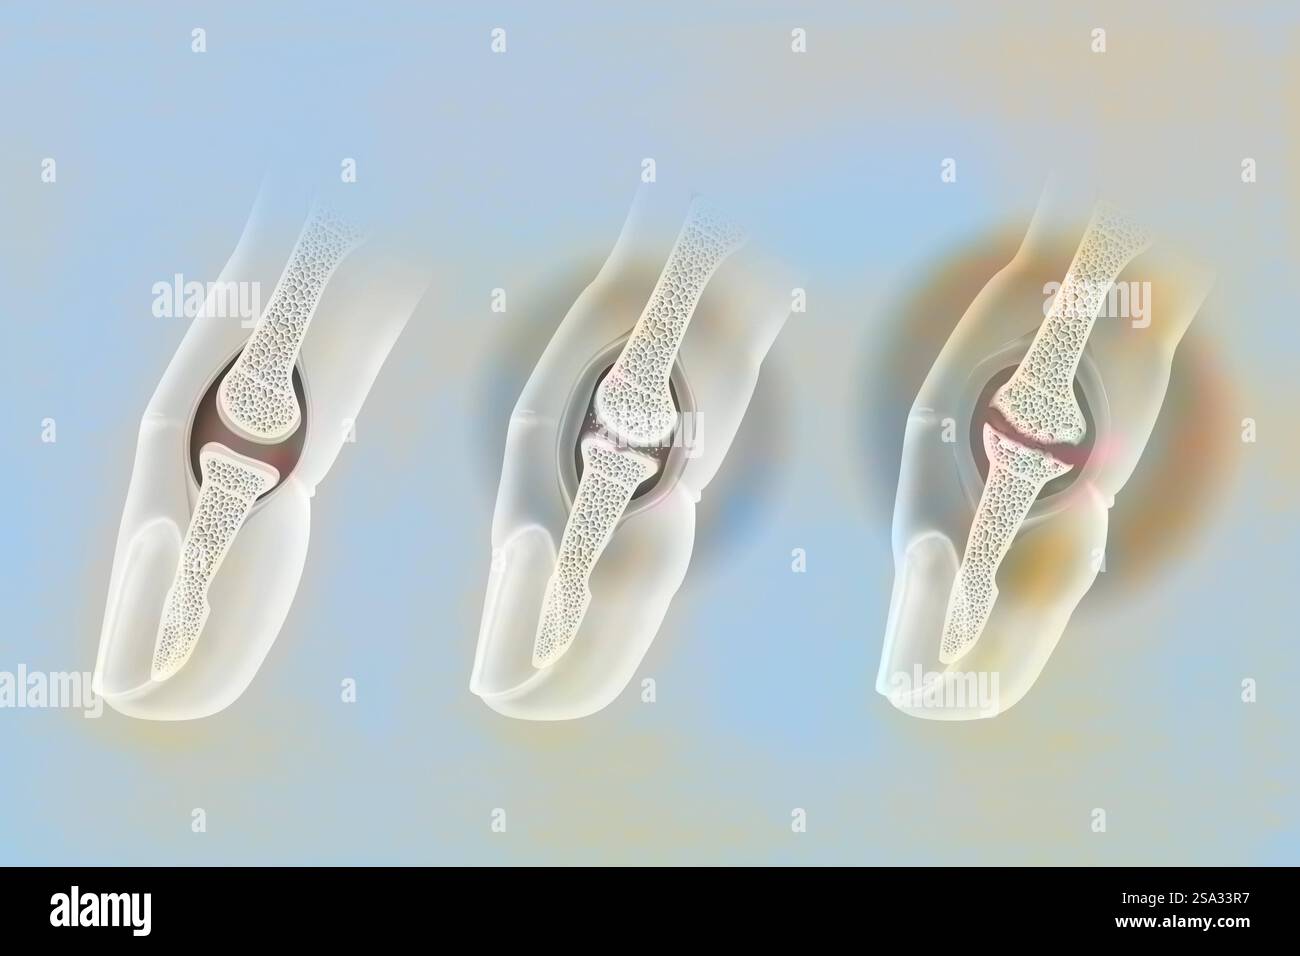

Finger osteoarthritis. Left: healthy joint. Middle: moderate osteoarthritis. The cartilage is worn, the cartilaginous debris causes inflammation of th Stock Photohttps://www.alamy.com/image-license-details/?v=1https://www.alamy.com/finger-osteoarthritis-left-healthy-joint-middle-moderate-osteoarthritis-the-cartilage-is-worn-the-cartilaginous-debris-causes-inflammation-of-th-image642999035.html

Finger osteoarthritis. Left: healthy joint. Middle: moderate osteoarthritis. The cartilage is worn, the cartilaginous debris causes inflammation of th Stock Photohttps://www.alamy.com/image-license-details/?v=1https://www.alamy.com/finger-osteoarthritis-left-healthy-joint-middle-moderate-osteoarthritis-the-cartilage-is-worn-the-cartilaginous-debris-causes-inflammation-of-th-image642999035.htmlRM2SA33R7–Finger osteoarthritis. Left: healthy joint. Middle: moderate osteoarthritis. The cartilage is worn, the cartilaginous debris causes inflammation of th